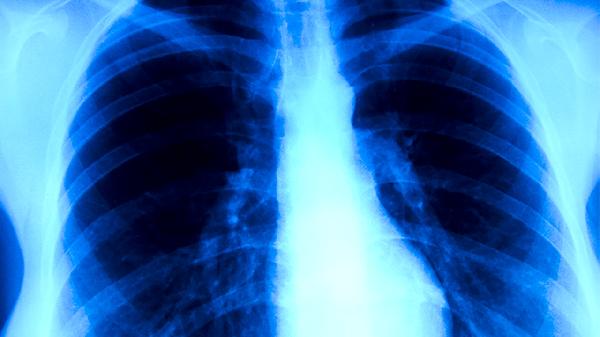

肺癌可能由吸烟、长期接触致癌物质、遗传因素、慢性肺部疾病、空气污染等原因引起。肺癌早期可能无明显症状,随着病情发展可能出现咳嗽、胸痛、咯血、呼吸困难等症状。建议及时就医,积极配合医生治疗,在医生的指导下服用合适的药物,并做好饮食调理。